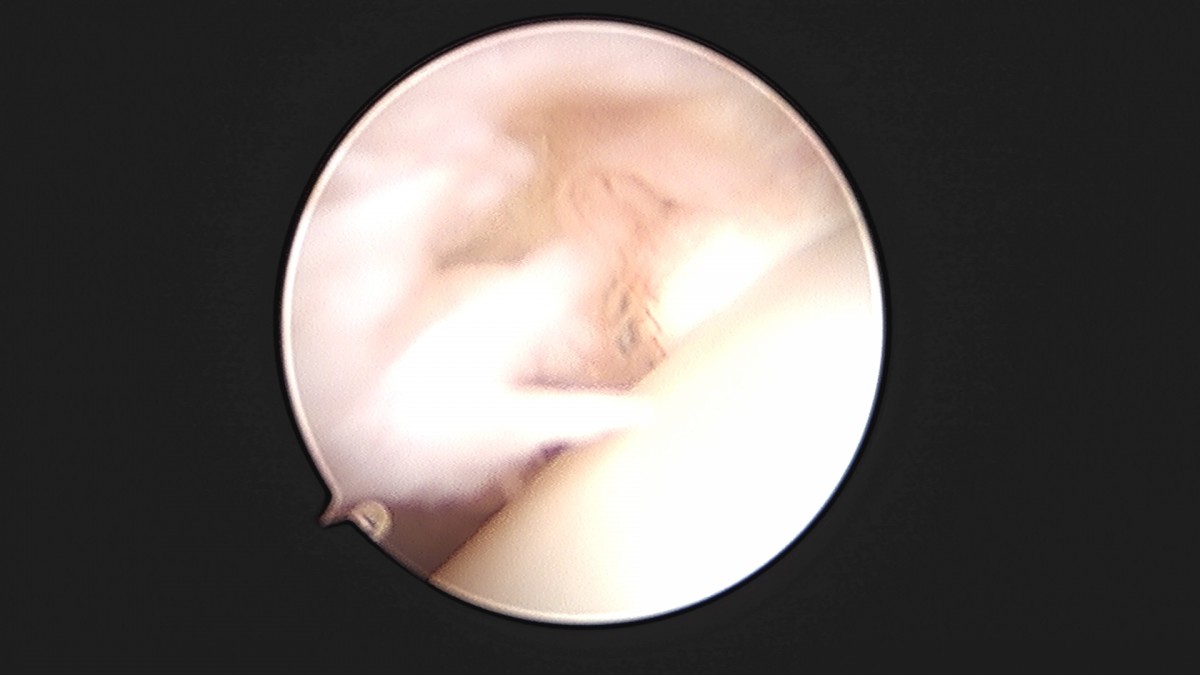

이재상원장님 발목 활액막 절제술 및 인대 봉합술 이승O 환자

작성자 최고관리자 댓글 0건 조회 787회 작성일 25-09-16 15:24